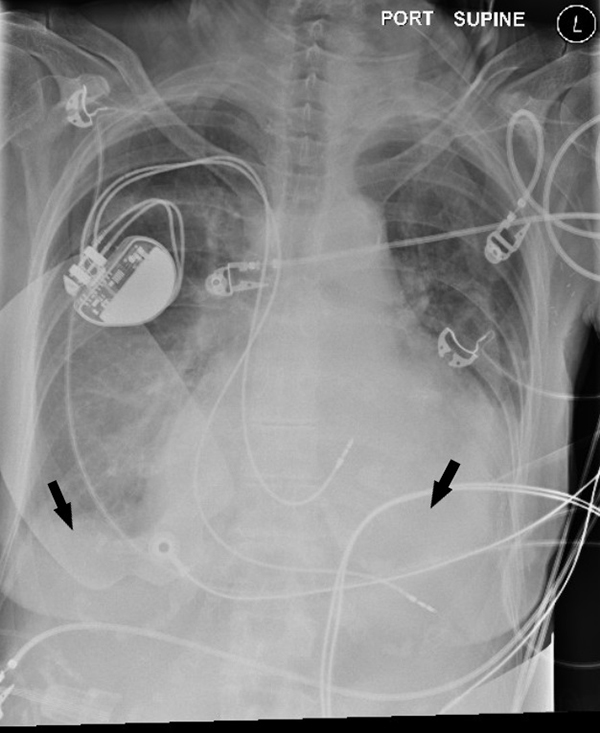

Laboratory work-up was notable for anemia, lactic acidosis, and elevated creatine phosphokinase (CPK) (Table 1). After stabilization, the patient was transported for imaging, where computed tomography (CT) of the head showed a small frontal hematoma and chest x-ray showed moderate bilateral pleural effusions (Figure 1). Additional CT imaging studies were obtained with no significant further findings. The patient's son arrived and provided information that the patient had a history of congestive heart failure and a pacemaker with an outdated battery and explained that his mother chose not to have the battery replaced. The son confirmed she did not desire any lifesaving intervention. The patient was then transitioned to comfort care, with the cessation of vasopressors and initiation of a fentanyl drip for pain, and was placed on hospice.

Figure 1. Chest x-ray showing bilateral pleural effusions (arrows)